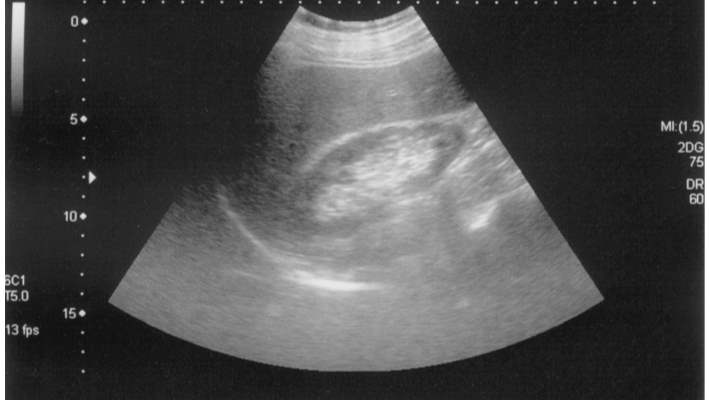

Safra Kesesi Polipleri